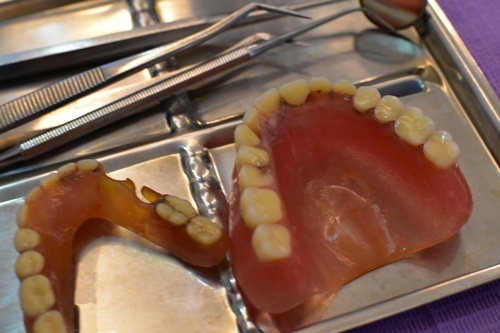

剛要67歲的阿嬤要去做全口重建。阿嬤在前年2018牙齒已經掉光光,透過政府的補助針對全臺65歲以上老人,提供活動假牙補助方案,於是阿嬤去做了活動假牙,但阿嬤戴活動假牙非常不習慣,假牙容易移動和有一些不舒服狀況,她一開始以為是還不適應,但已經過了兩年阿嬤還是未能適應政府補助活動假牙帶來的不適感。阿嬤吃飯時寧願用牙齦吃飯,也不願意戴上活動假牙,她說不方便,只有外出時因為美觀問題才會戴上假牙。我覺得有些可惜。

阿嬤其實在這兩年來瘦了很多,可能是缺牙原因,以前愛吃美食的她現在總是食慾不好。身體漸漸出現沒力的狀況,媽媽時常給她喝滴雞精補充體力,但這個方法治標不治本。所以媽媽和家人商量後決定要幫阿嬤做全口重建幫助她重新愛上美食,享受人生。

吳醫師對植牙患者特別謹慎,不想讓患者白花錢。對於不能植牙的患者吳醫師會另外替患者找出最適合的治療方法。諮詢師說現在植牙費用都是單顆計費,一顆要價4-10萬,對許多有缺牙困擾的患者來說,是一項很大的經濟負擔,因此,除非只缺幾顆牙就可以考慮單顆植牙,但如果缺很多顆牙就可以考慮以「植牙搭配覆蓋式活動假牙」取代全口植牙,這樣不僅手術費用較省,耐用度和美觀也都不錯。植牙只需植4個地方固定好再搭配覆蓋式活動假牙,這也是CP值最高方案。